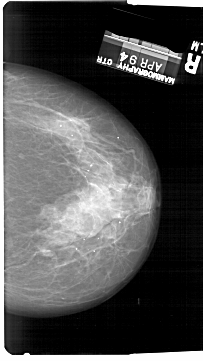

A_1728_1.LEFT_CC

LEFT_CC LINES 6286 PIXELS_PER_LINE 3586 BITS_PER_PIXEL 12 RESOLUTION 43.5 OVERLAY